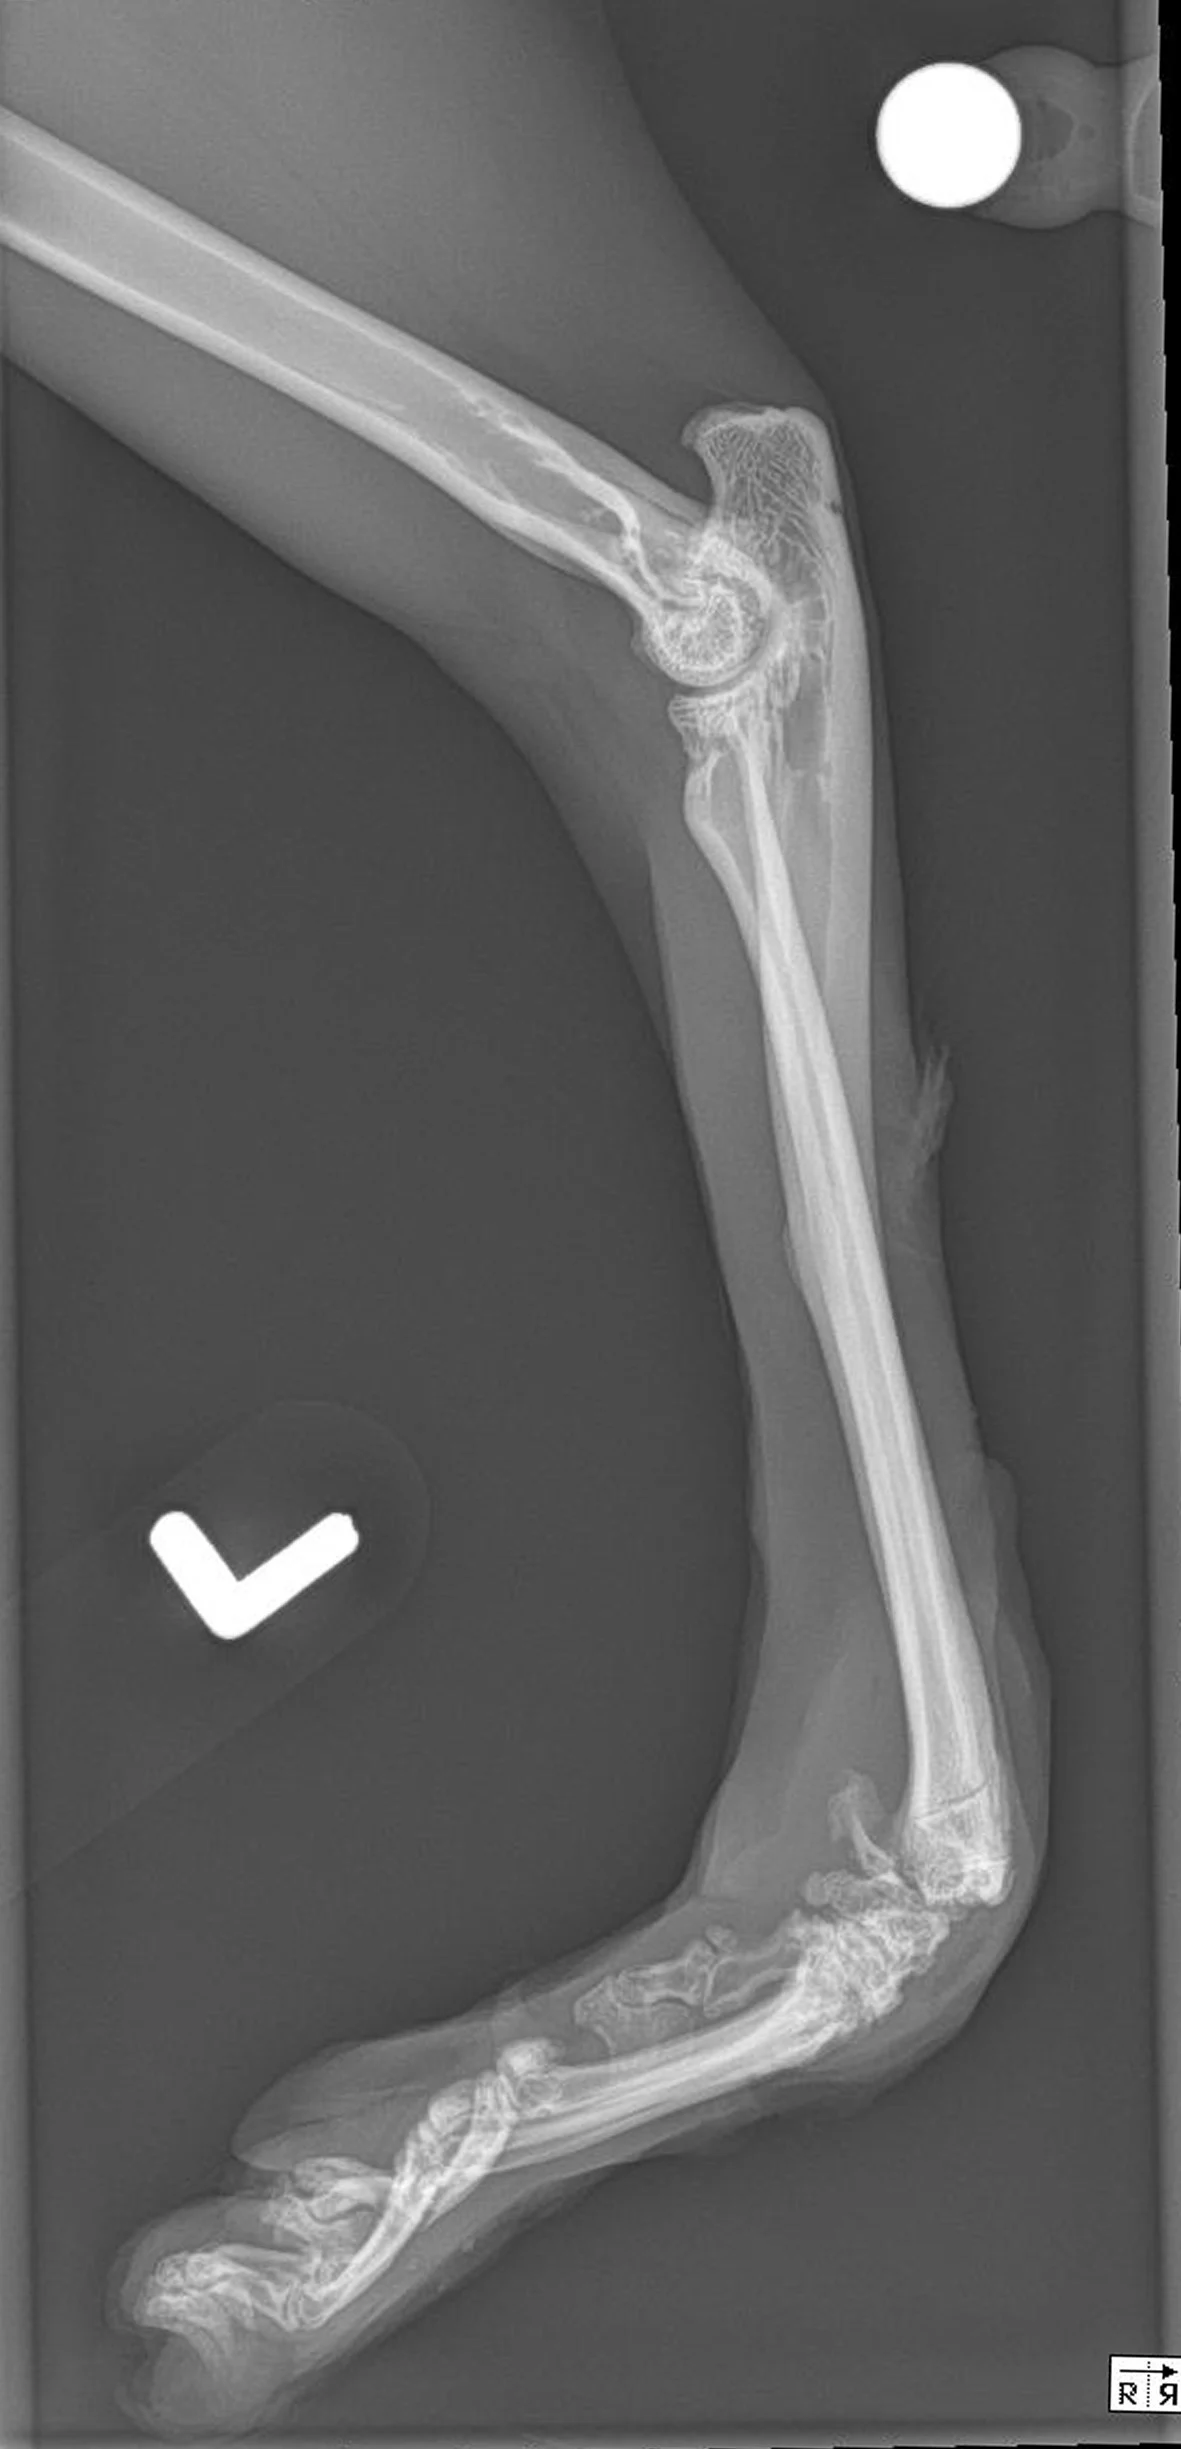

Case 1: Congenital Musculoskeletal Defect

Figure 1 A 2-year-old cat was presented for a congenital musculoskeletal defect that included bilateral hyperflexion of the carpi and 180-degree torsion of the left manus. Chronic weight-bearing had resulted in a thickened left dorsal carpus, lack of epithelium, and fine granulation tissue. Initial treatment included bilateral superficial and deep digital flexor tendon transections, right carpal arthrodesis with plate fixation and postoperative carpal splinting, and left carpal arthrodesis with external skeletal fixation. A skin graft was recommended but declined by the owner. A nonadherent, cuttable, hydrophilic foam dressing, cast padding, and self-adhesive wrap were applied and changed every 3 to 7 days.